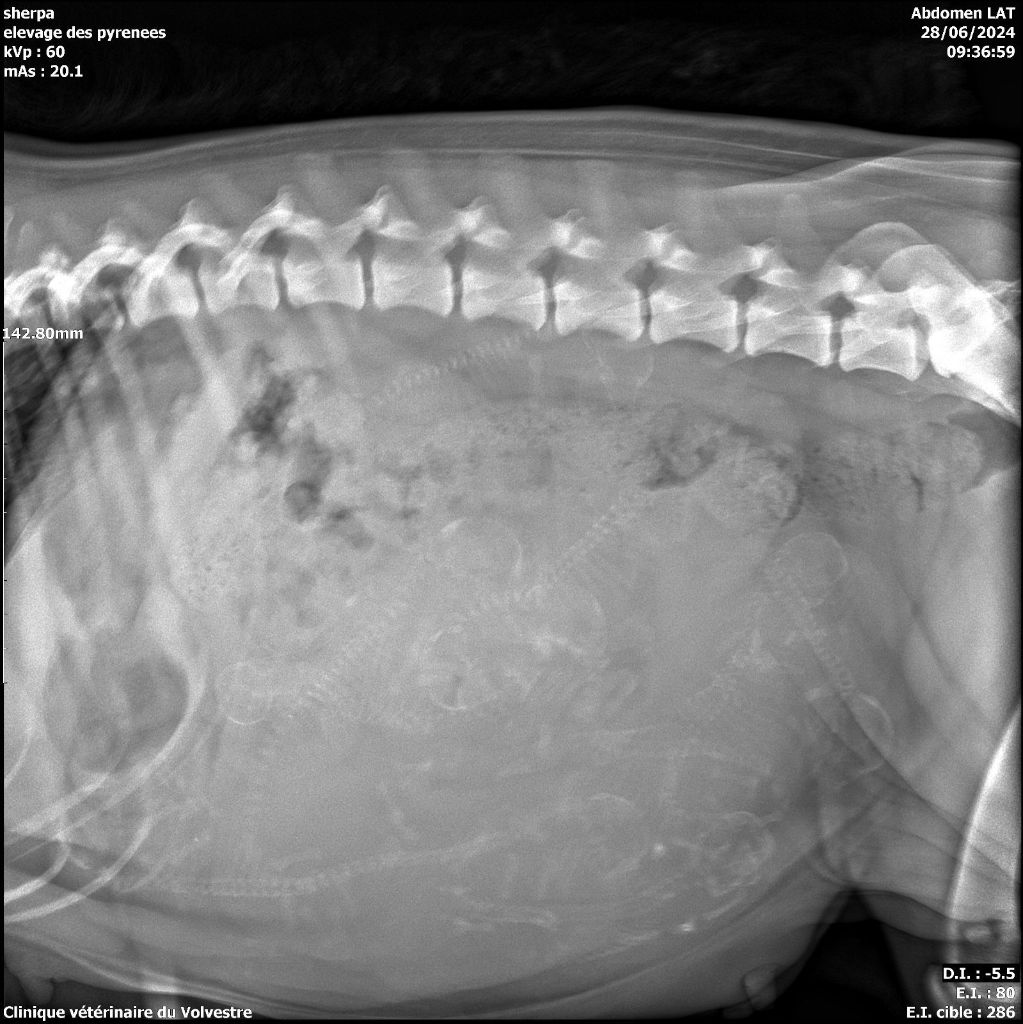

Radios de gestation de Sherpa....

28/06/2024

Nous avons fait la radio de gestation à Sherpa ce matin, 10 petites têtes on était vue!!

plus que quelques jours a attendre, pour voir leurs petites frimousses... trop h&aci...